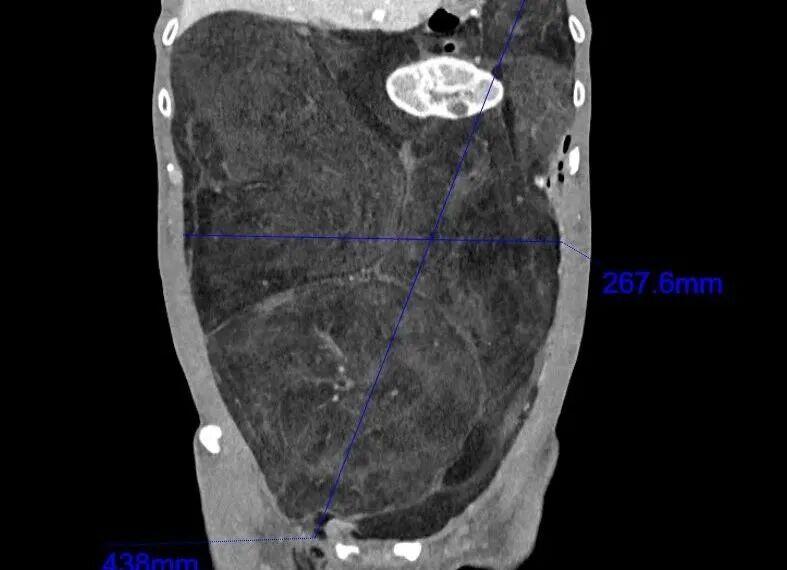

8月初,老邹慕名来到浙大二院肿瘤内科就诊。入院后,医生安排他做了腹部增强CT和肿瘤穿刺活检。腹部CT提示:巨大的肿瘤从左上腹一直延伸到右下腹及盆腔,最长径达40厘米,前后径也有20厘米,几乎“填满”了整个腹腔。肿瘤穿刺病理提示:腹膜后高分化脂肪肉瘤。

“从腹部CT上看,患者内脏器官已经被这个肿瘤挤压得明显移位了,小肠和胰腺被挤到了左上腹靠近膈肌的位置,右肾完全被肿瘤组织包绕,被挤压至身体左侧,原本在腹腔右侧的升结肠和阑尾被挤到了左侧腹腔。腹腔内几乎所有的脏器都改变了原有的位置。”焦裕荣医生说,“如果不选择手术,肿瘤会持续增大,上抬膈肌导致呼吸抑制;进入腹腔盆腔薄弱区域,导致腹股沟疝气等一系列并发症的发生。”